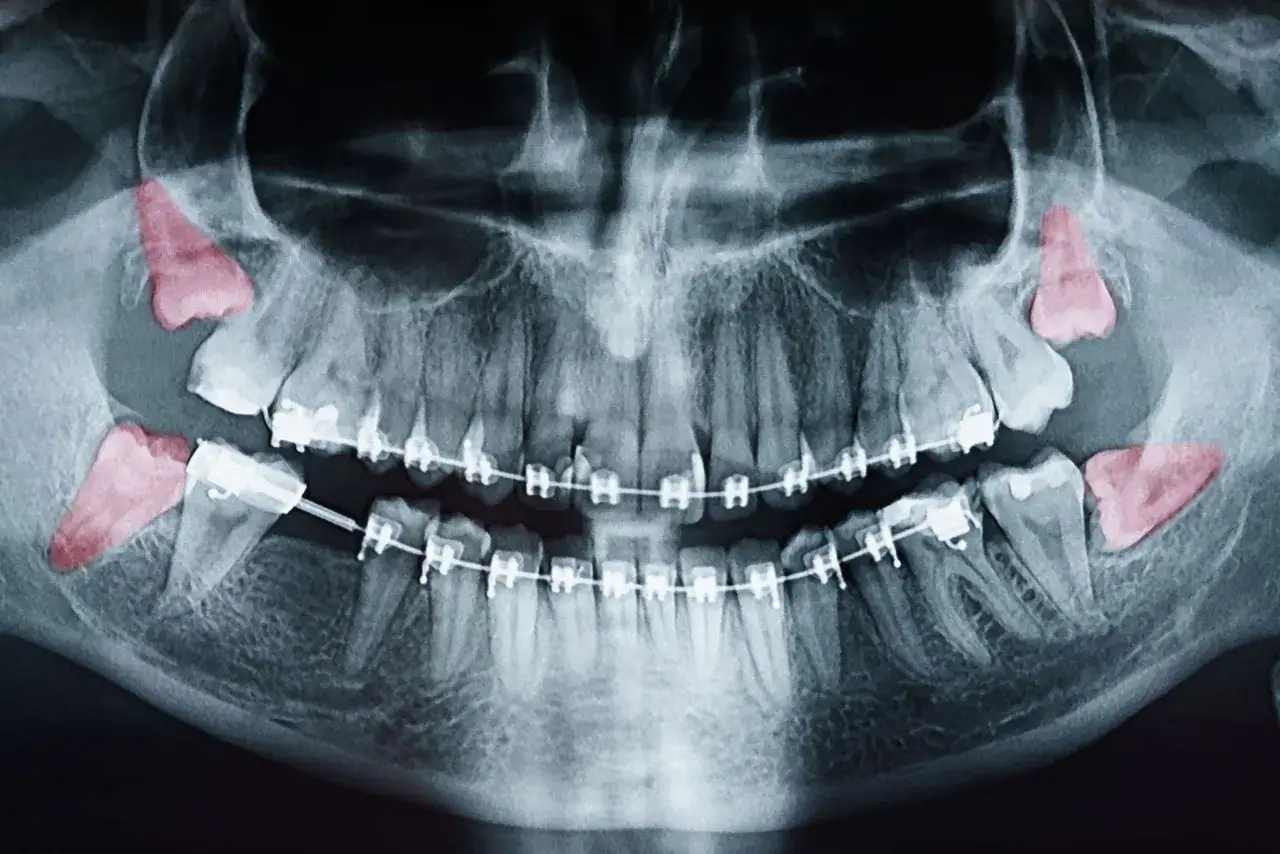

Przed samym zabiegiem zawsze odbywa się konsultacja u chirurga stomatologa. Jest to ostatni, ale niezwykle ważny etap kwalifikacji. Podczas tej wizyty chirurg dokładnie oceni stan Twojego zęba i całej jamy ustnej. Omówi z Tobą szczegółowy plan zabiegu, wyjaśni możliwe ryzyka i odpowie na wszystkie Twoje pytania. To doskonała okazja, aby rozwiać wszelkie wątpliwości. Często na tym etapie wykonuje się lub analizuje zdjęcie pantomograficzne, które jest kluczowe dla precyzyjnego zaplanowania ekstrakcji.

Czy zdjęcie pantomograficzne jest zawsze w cenie?

Zdjęcie pantomograficzne, czyli panoramiczny rentgen zębów, jest niezwykle ważnym badaniem diagnostycznym przed usunięciem ósemki. Pozwala chirurgowi ocenić położenie zęba, jego korzenie oraz relacje z sąsiednimi strukturami, takimi jak nerwy. Dobra wiadomość jest taka, że zdjęcie pantomograficzne jest refundowane przez NFZ, ale tylko wtedy, gdy jest wykonywane w ramach przygotowania do zabiegu chirurgicznego usunięcia ósemki. Oznacza to, że jeśli lekarz uzna je za niezbędne do prawidłowego zaplanowania ekstrakcji, nie poniesiesz za nie dodatkowych kosztów. Jeśli jednak wykonasz je prywatnie, bez skierowania na zabieg NFZ, będziesz musiał pokryć jego koszt.